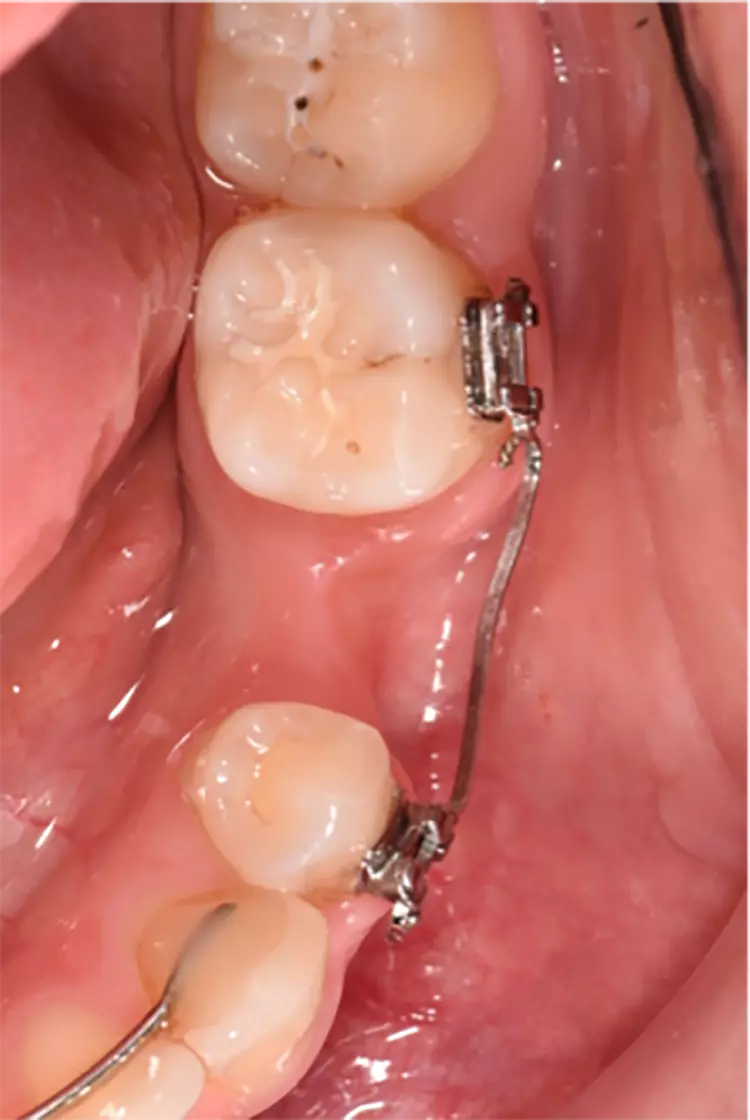

Die Implantate wurden im üblichen chirurgischen Vorgehen inseriert und sofort mit einem Provisorium aus Polymethylmethacrylat (CAD-Temp, VITA) versorgt, wobei die Provisorien außer Okklusion geschliffen wurden und darauf geachtet wurde, dass approximal nur sehr schwache Kontakte bestanden (Abb. 3a bis e). Die definitive prothetische Versorgung erfolgte im Unterkiefer nach frühestens 2 Monaten, im Oberkiefer nach frühestens 4 Monaten. Die Restaurationen wurden aus verblendetem Zirkonoxid hergestellt (VITA YZ HT / VITA VM 9, VITA).

Bei Knochendefekten ist eine Augmentation erforderlich. In der klinischen Studie „FR/ZH“ wurden in 11 Fällen kleinere simultane Augmentationen durchgeführt (vergl. Abb. 3). Die Augmentationen dürfen aufgrund der ermittelten Sondiertiefen und Röntgenbefunde als erfolgreich angesehen werden.